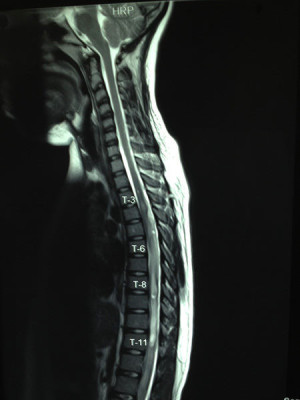

Casos Neuroloquirúrgicos

Envíado por Dr. Ruben Eduardo Amaya Contreras